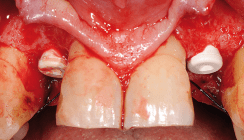

Foto: © Vera Kuttelvaserova – Fotolia.com/SDS Swiss Dental Solutions AG

Keramik hat in der Zahnmedizin eine große Tradition und wir wissen aus der Prothetik, dass sich keramische Gerüste sehr bewährt haben. Durch die Hochleistungskeramiken sind wir in der Lage, im Bereich des festsitzenden Zahnersatzes bei Kronen, Brücken aber auch bei implantatgetragenen Primär-, Sekundär- oder sogar Tertiärstrukturen qualitativ hochwertige vollkeramische Restaurationen herzustellen. Aus biologischen und ästhetischen Aspekten heraus, kann man wirklich sagen, dass Keramikimplantate inzwischen als Alternative zu Titanimplantaten anzusehen sind, wobei jedoch die mechanischen Eigenschaften noch weiterhin erforscht werden müssen, um eine echte mechanische Gleichwertigkeit zu beweisen.

Es ist unbestreitbar, dass die biologischen und ästhetischen Eigenschaften von keramischen Implantaten sehr im Vordergrund stehen. Bisher bestand der Markt hauptsächlich aus einteiligen Implantaten, inzwischen werden vermehrt zweiteilige Keramikimplantate angeboten, weil man erkannt hat, dass einteilige Implantate ein beschränktes Indikationsspektrum haben und oft mit prothetischen Nachteilen verbunden sind.

Die Datenlage zu vollkeramischen Implantaten ist gering, aber es gibt inzwischen Studien, welche von einer Vergleichbarkeit der Überlebensraten bei Vollkeramik- und bei Titanimplantaten berichten, jedoch nur über einen relativ kleinen Zeitraum gesehen. Zusammenfassend sehe ich die sogenannten weichen Faktoren bei den Keramikimplantaten deutlich im Vordergrund stehend.